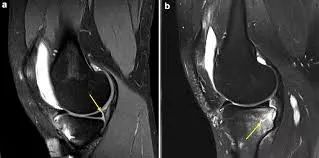

Hash等指出,Ramp损伤在MRI上的最突出 标志是在内侧半月板后角与后内侧关节囊之间插入了一个薄层的液体信号,观察内侧半月板后角与滑膜分离征象。

病例图片(均来自网络):